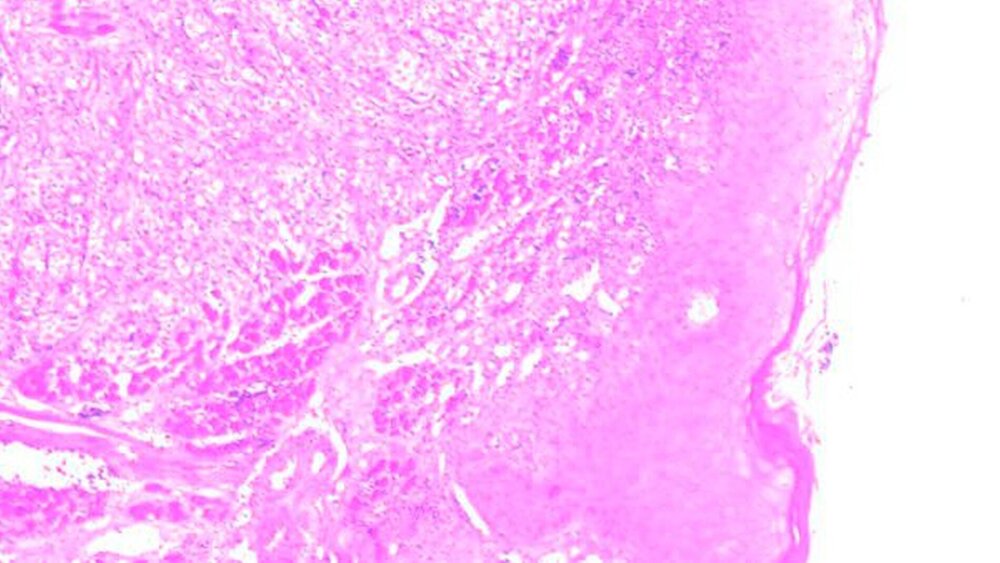

Zur Befundsicherung der intraoralen Neoplasie erfolgte eine Probeentnahme in Lokalanästhesie / Stand-by. Das Ergebnis der pathohistologischen Untersuchung bestätigte den Verdacht auf eine Metastase des bekannten epitheloiden Mesothelioms. Die immunhistochemische Untersuchung zeigte Tumorzellen, die eine starke Positivität für Calretinin aufwiesen, darüber hinaus einen starken Nachweis von Gesamtcytokeratin sowie Cytokeratin 5/6 (Abbildungen 2a und b).